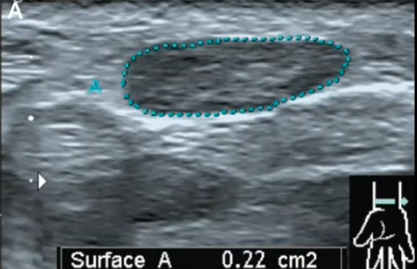

Nerfs : comment je fais une échographie d'un nerf, neuropathie (hors pied diabétique)

ACID S. – UCL

Année académique 2022-2023

Musculo-squelettique US Nerf DES SPECIALITE